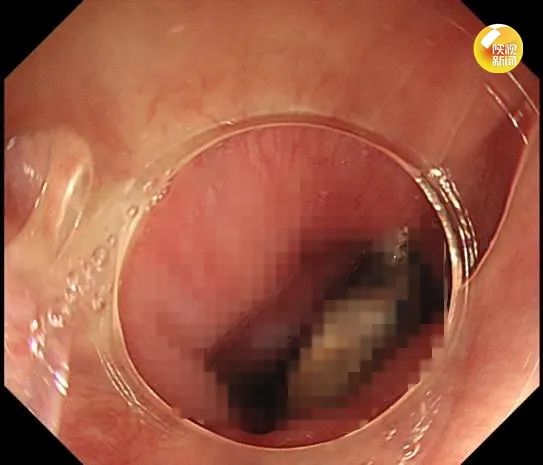

近日,西安的王先生在吃红枣粽子时,突然感到咽部刺痛,无法吞咽。他通过反复咳嗽、拍打都没能缓解,意识到可能枣核卡在了喉咙,于是前往医院。

经检查,枣核体积偏大而且两侧尖锐,医生决定通过内镜取出。几分钟后,这枚约3.2cm长的枣核被顺利取出。目前,王先生已出院。